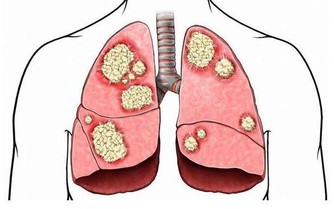

喝酒其實會帶給身體很多不同的負擔,像說高血壓跟增加心臟疾病的可能性。